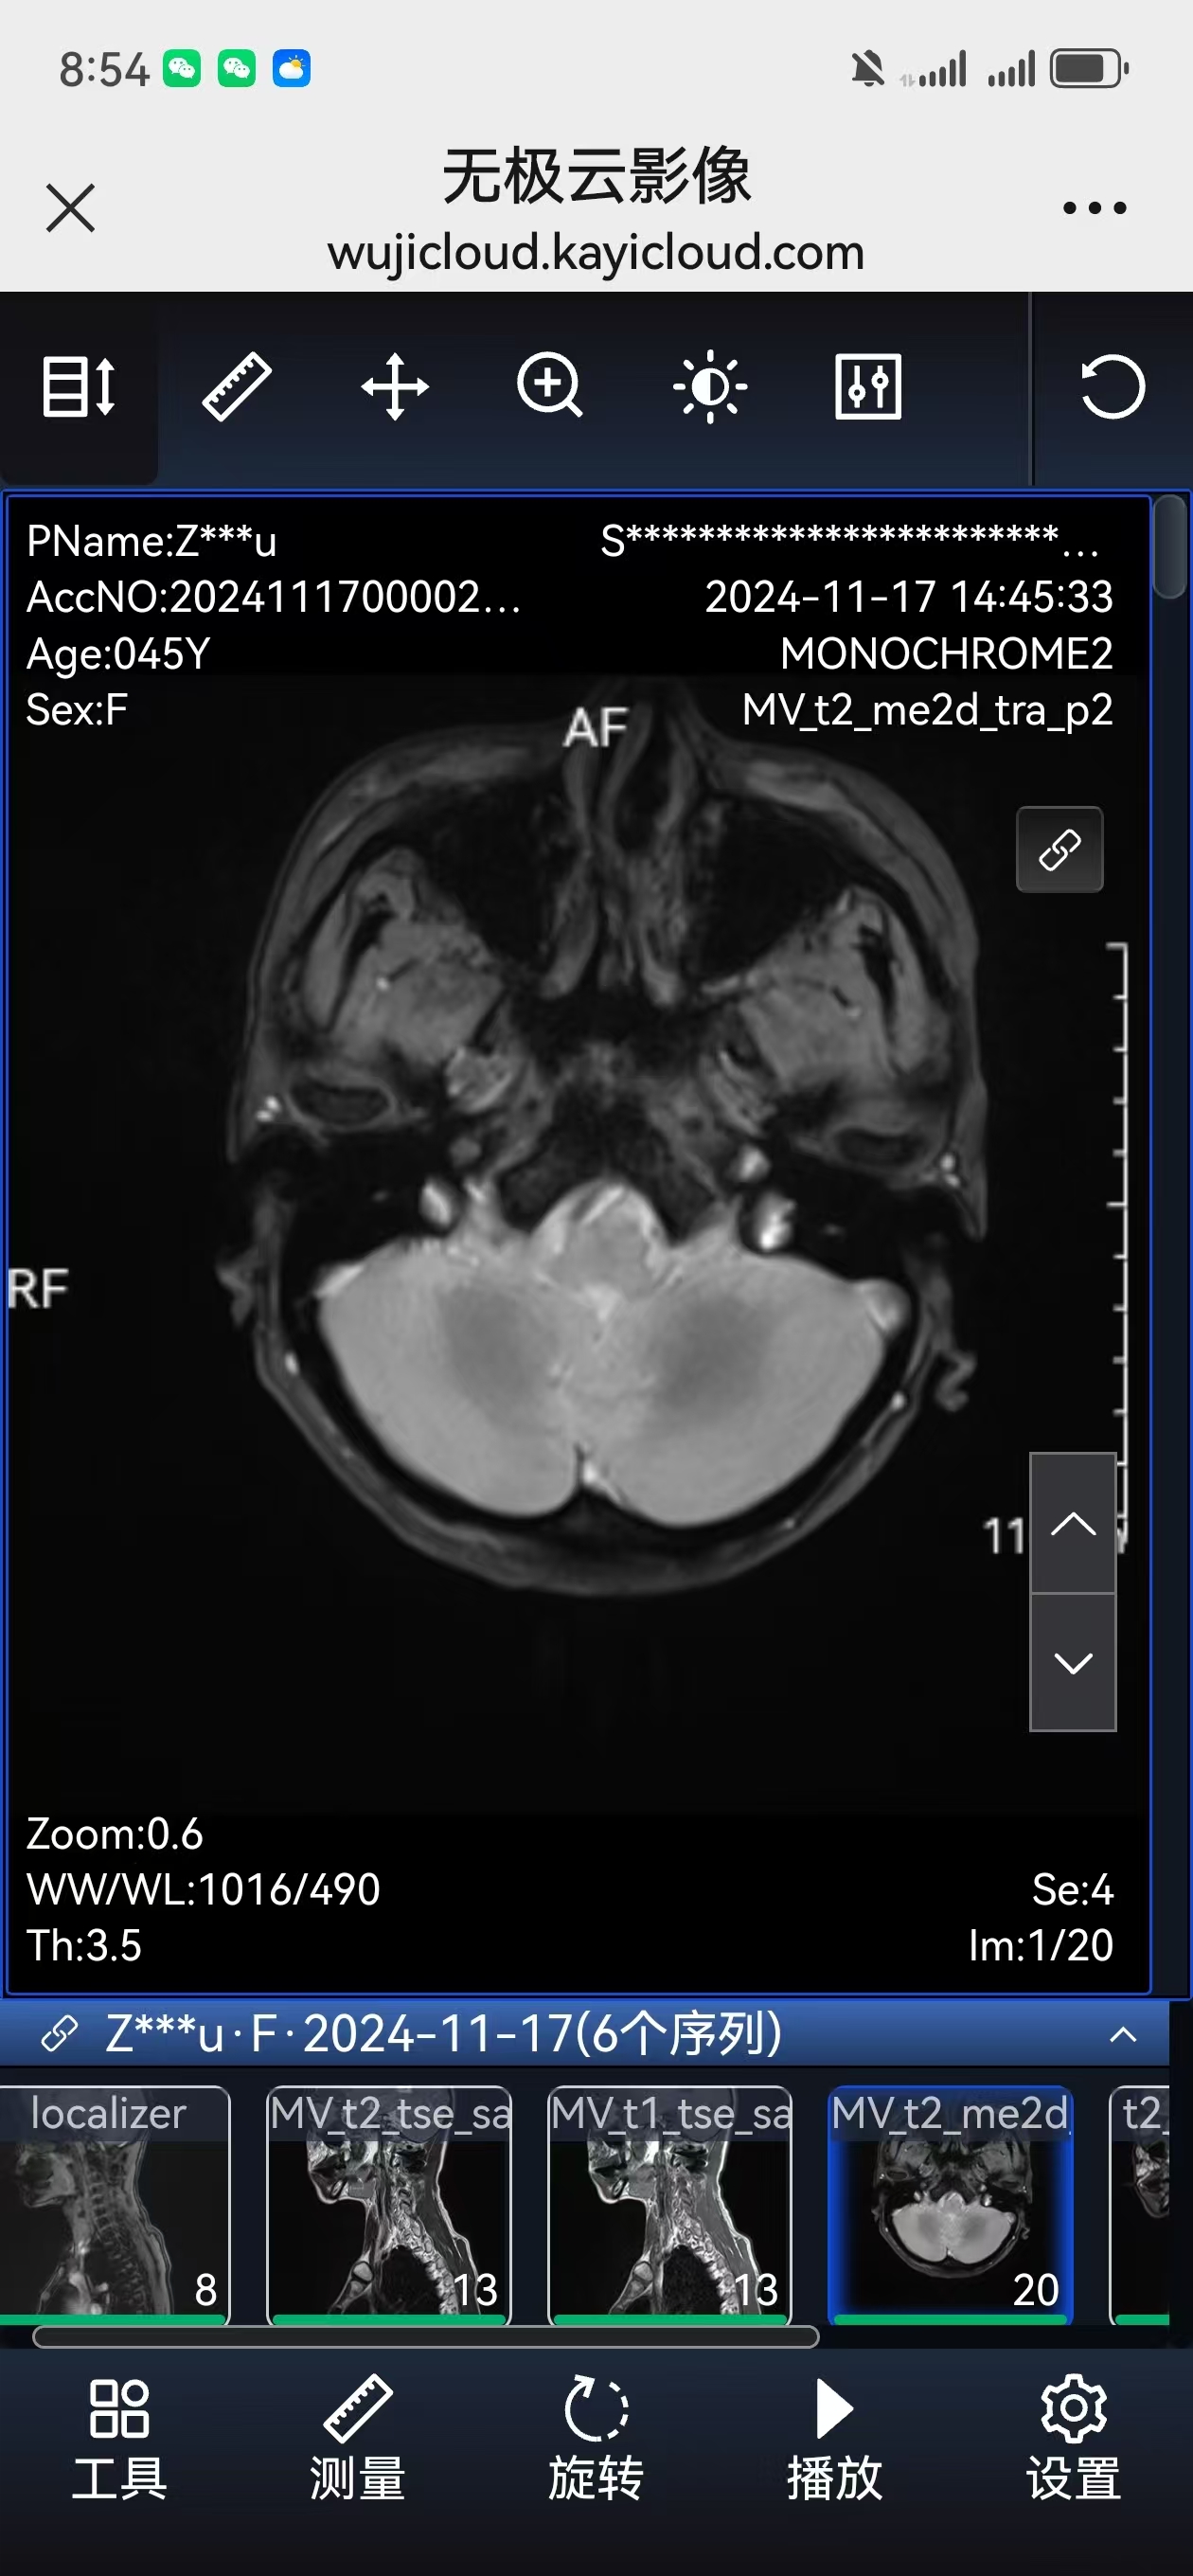

• 术后影像: